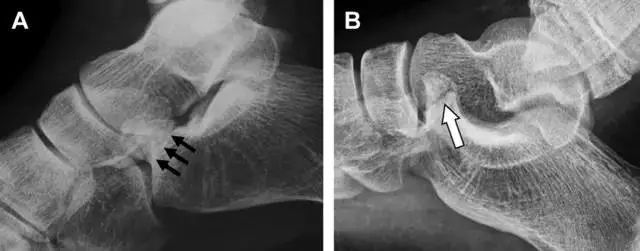

趾短伸肌跟骨撕脱性骨折

另一种重要的跟骨撕脱性骨折,于足内翻时发生在趾短伸肌的起点处。观察来自跟骨背外侧的、不同大小的骨折块,前后位 X 片最适合不过了(图 7)。

图 7 溜冰受伤的患者,趾短伸肌跟骨撕脱性骨折。正位片示 2 个骨折块(箭头)来源于跟骨前外侧、趾短伸肌的起点处。踝关节外侧远端是否存在软组织水肿是一个重点观察点。

跗跖关节复合体(Lisfranc 关节复合体)损伤

与跗跖关节韧带相关的骨折常由旋前或旋后的跖屈损伤引起。尽管跗跖关节骨折脱位仅占所有骨折的 0.2%,但是约 20% 的这些骨折在初次检查时被漏诊。初次 X 片可能示正常,但是负重位 X 线片常常提示脱位或半脱位。

典型表现:第二跖骨底和内侧楔骨之间的骨折碎片,跖骨间间隙增宽(图 8)。脱位亦可发生在舟骨-内侧楔骨关节,导致另一种变异的跗跖关节损伤(图 9A)。此外,骰骨的小块皮质撕脱在足部斜位片上可清晰显示(图 9B)。

图 8 从马上摔落的患者,跗跖关节骨折。A 正位片示内侧楔骨旁边的小骨折碎片(箭头),第二跖骨底向外半脱位;B 负重位侧位片示第二跖骨相对中间楔骨向背侧轻微移位(长方形);C STIR 序列 MRI 图像示跗跖关节韧带断裂(箭头),第一至第三跖骨、内侧楔骨及中间楔骨均骨髓水肿。

图 9 变异的跗跖关节骨折。A 另一种类型的跗跖关节损伤,中间楔骨向内侧半脱位(弧形箭头),从而使第一、第二跖骨间间隙变宽,需注意,骨折在靠近内侧楔骨处(箭头);B 外侧跗跖关节损伤伴随从骰骨跖骨韧带的骰骨撕脱(箭头),需注意,第五跖骨底近端处存在软组织水肿(空箭头)。